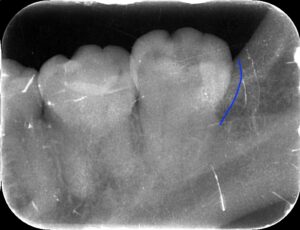

レントゲンでは白いセメントが歯の形態に

合わせてきれいに詰められています。